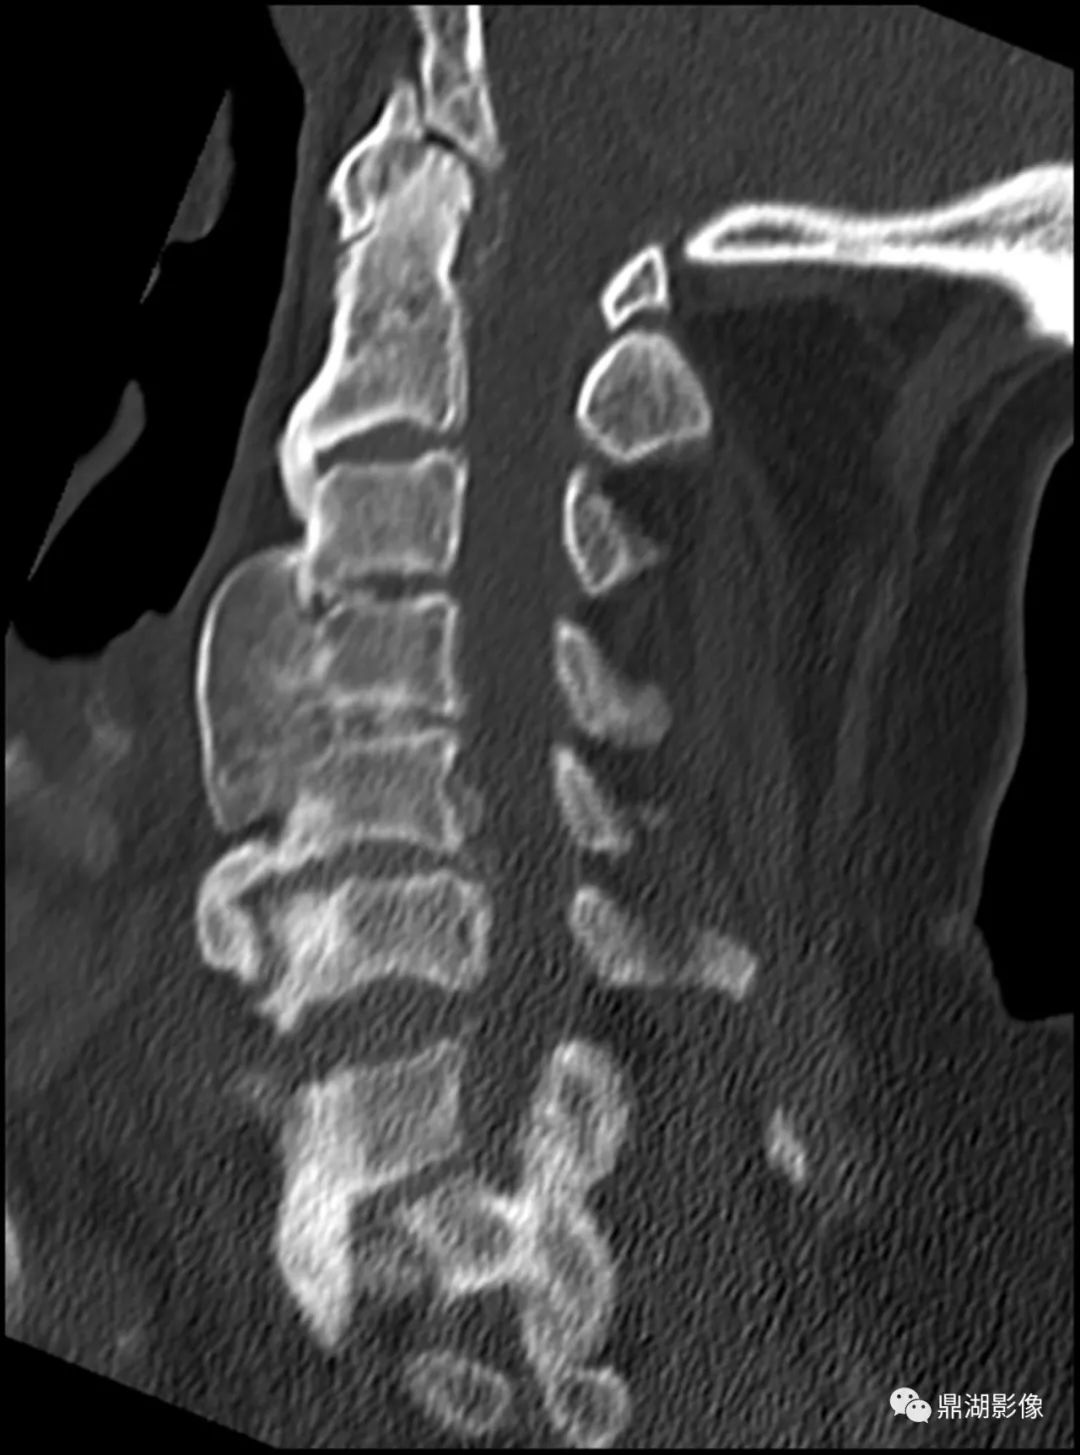

- 椎体前外侧连续性骨化,后纵韧带、黄韧带也可受累非边缘性韧带骨赘,即骨化不发生于间盘边缘,形成波浪样外观

- 随时间进展骨化厚度可从1-2mm增至20mm

- 椎间隙高度正常

非边缘型骨赘

边缘型骨赘